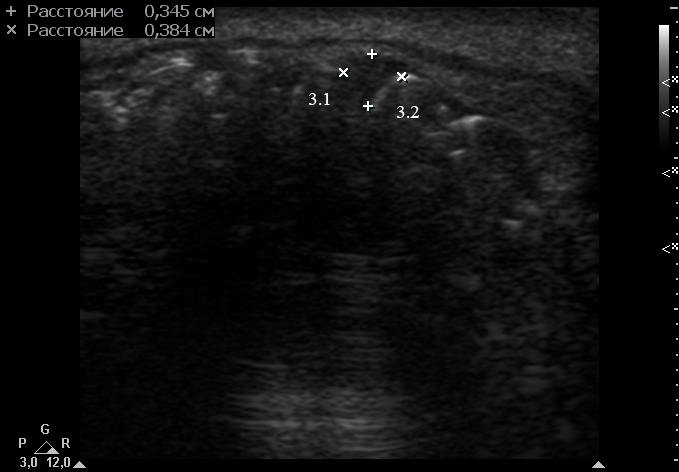

An extraoral ultrasound examination was performed by O.S.C., an expert physician (>18 years of experience in head and neck USG), on the day of admission in the department. A HD11 XE USG system (2007, the Philips, Amsterdam, the Netherlands) equipped with a linear L12-3 transducer (frequency fange: 3.0-12.0 MHz; aperture: 38 mm) was used for the examination, fixing a 3-cm of ultrasonography (penetration) depth.

Anterior part of the neoplasm at the vestibular aspect of the lower teeth measured 0.34 x 0.38 cm (Fig 3). Upon the gray-scale USG the anterior part portion of the neoplasm vizualized as homogenous hypoechoic lesion with no signs of calcifications. Color Doppler USG showed no vascularity within the vestibular portion of the neoplasm (Fig 4).